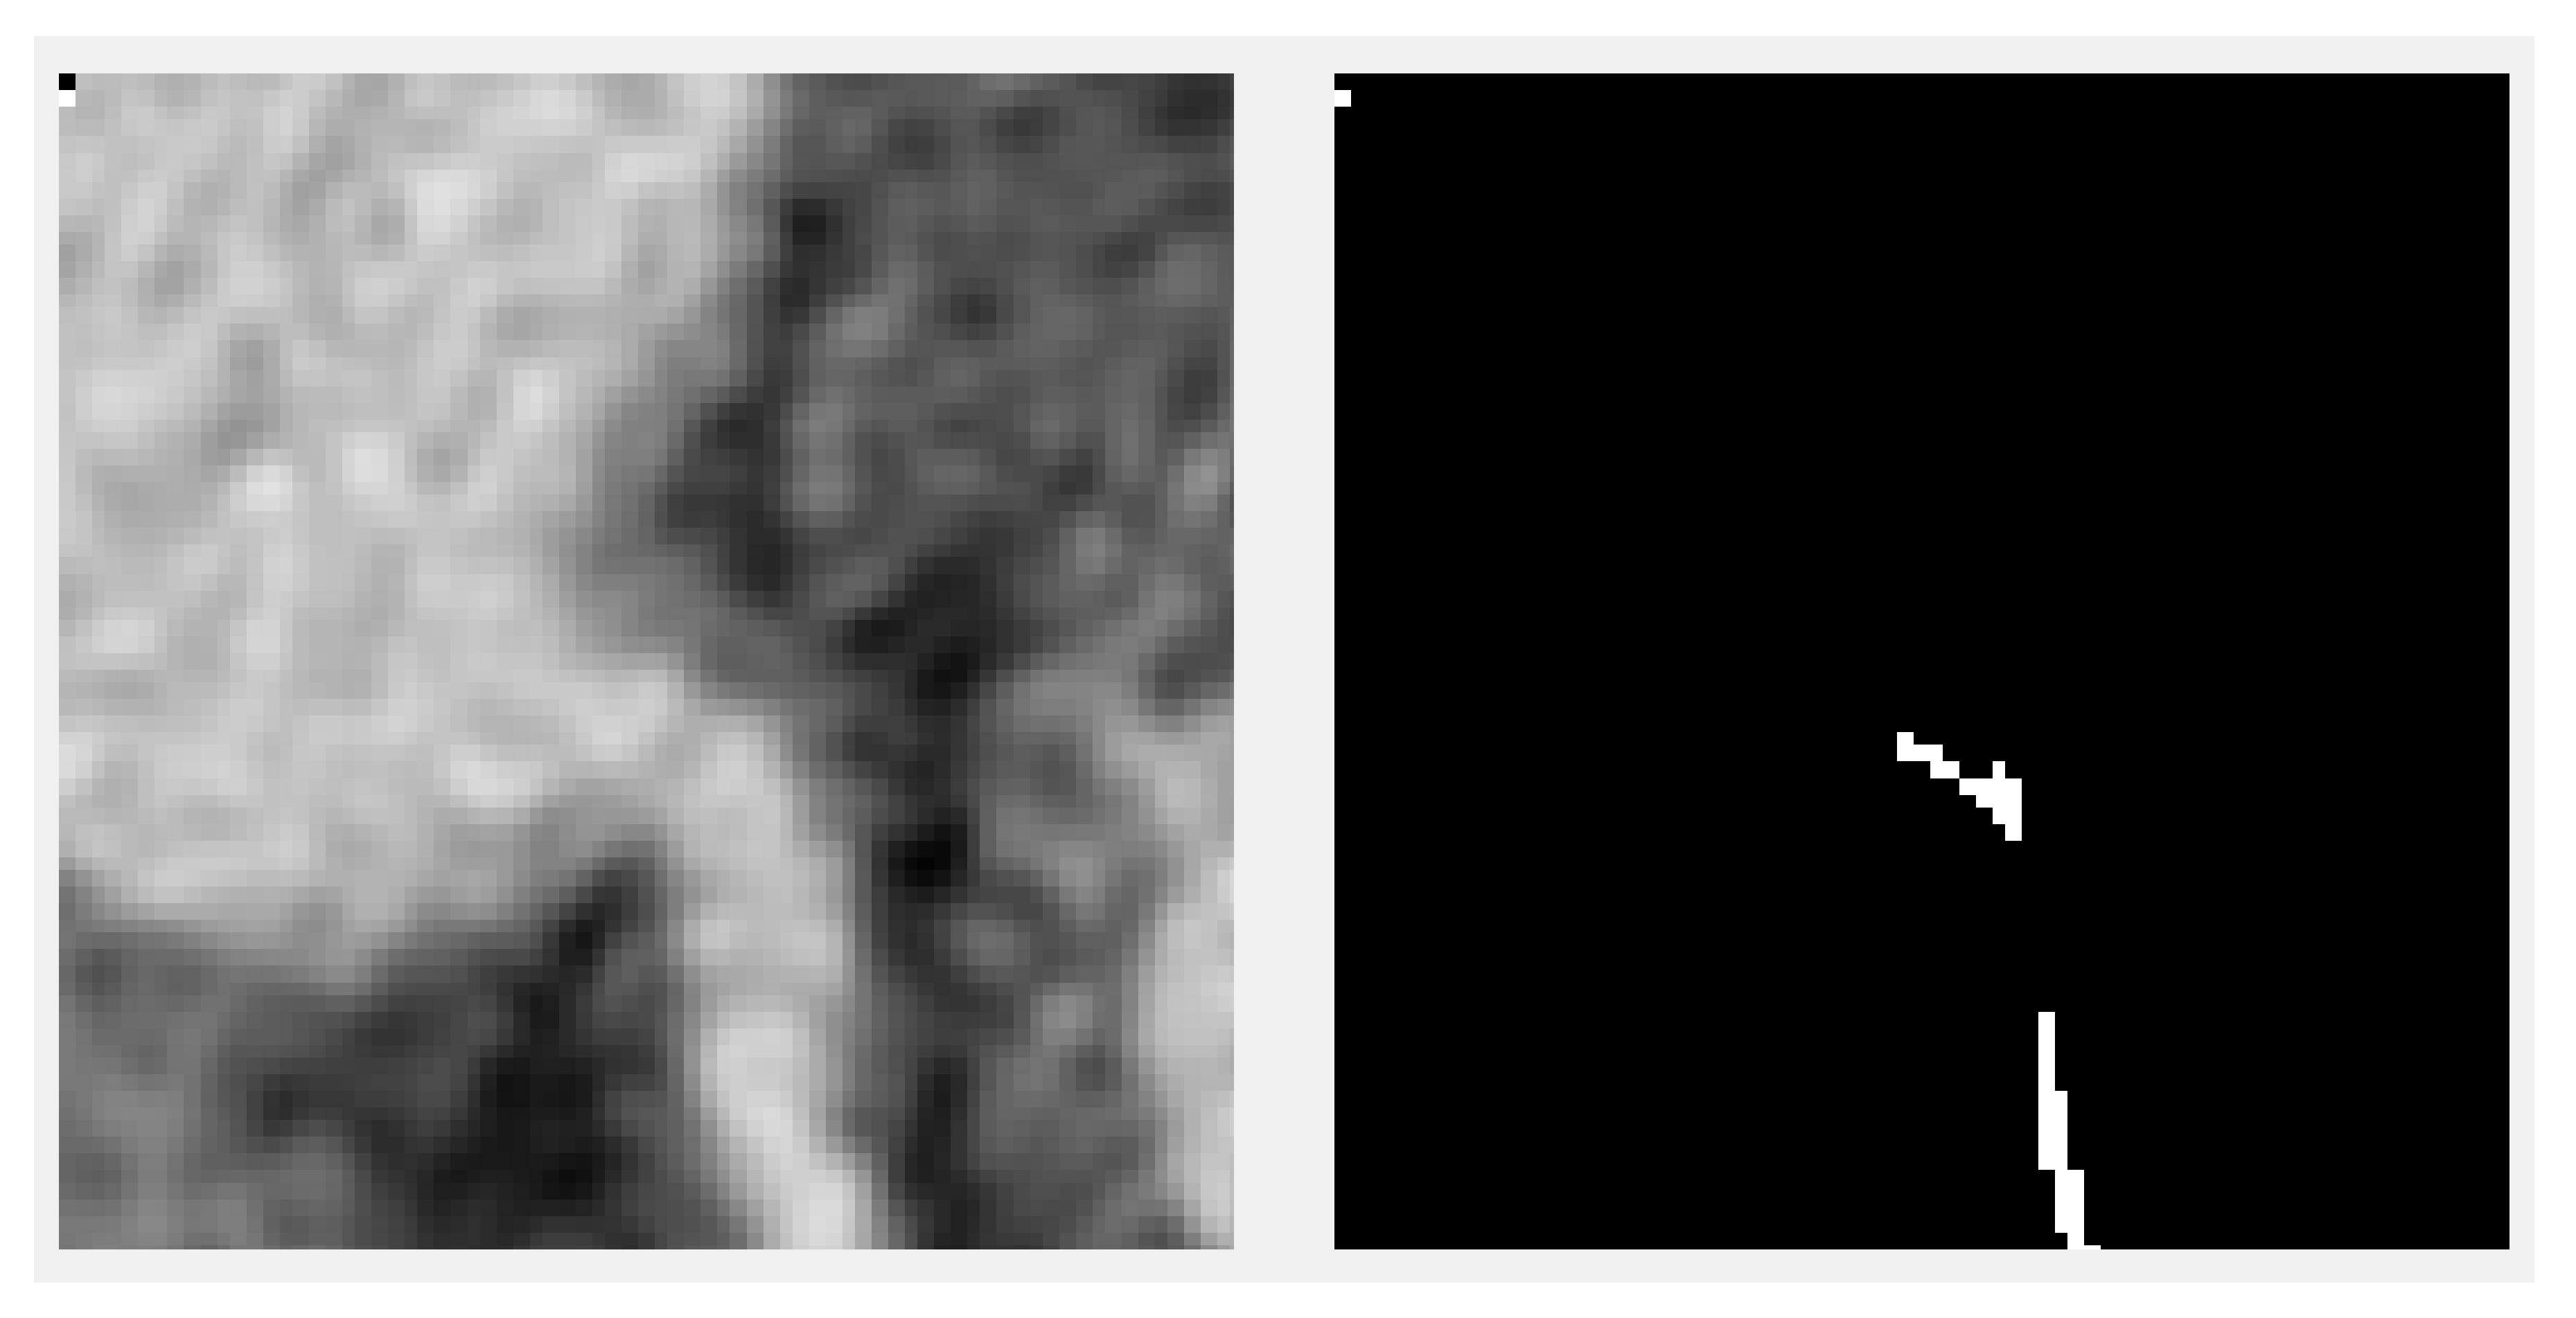

Our first approach was to resize the volumes (and the ground truth) to a volume that would be small enough to fit in the video RAM but large enough not to lose the details needed for segmentation. The first drawback was that the volumes from the benchmark did not come in a standard size. The X- and Y-axis were always of size 512, but the Z-axis ranged from 272 to 388. This meant that the aspect ratio after any resize to a fixed value would not be constant. Another important loss would be the impossibility to have augmentation under the given circumstances since even the 90-degree rotations would cause big ratio changes. The second drawback of this method was the loss of precision when upscaling. Extracting the centerline would imply getting as good a precision as possible since the vessel fitting algorithms that take as input a centerline depend on this accuracy. Upscaling precision loss can be observed in Figure 2, in which the ground truth centerline is discontinuous and inhomogeneous. Any algorithm without 100% precision would result in something even worse. Training the model using resizing posed problems with the dataset being too small.

Figure 2.

Downscaled and upscaled centerline ground truth (80 × 80 × 64) plotted in 3D to highlight the difficulty of using it for training.

A second approach was proposed to divide the input into smaller patches, cutting only small parts of the volume (and the ground truth) and feeding them to the network. An example slice of a patch together with the associated ground truth is shown in Figure 3. This method does not have any of the downsides of the previous one but introduces a different one—the lack of context. Therefore, a tradeoff is reached between increasing the patch size so that the available contextual information for the model is enough to make a good prediction and the size of the model so that the model is large enough to capture the correlations about where the centerline is positioned and that it should be continuous and also cross the patches.

Figure 3.

A 2D slice of an augmented patch with ground truth next to it.